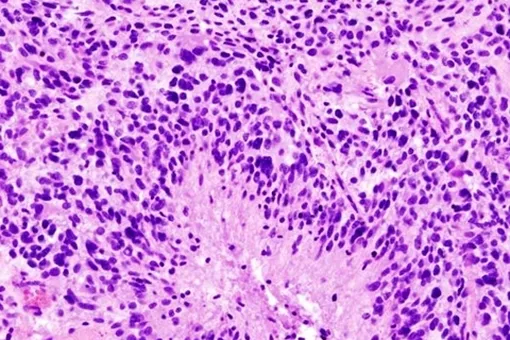

Ученые использовали передовые методы визуализации на мышах с двумя типами глиобластом. Оказалось, что опухоли вызывают эрозию костей черепа, особенно вдоль швов, где кости срастаются. Компьютерная томография пациентов подтвердила: у людей с глиобластомой толщина черепа уменьшается в тех же анатомических зонах, что и у мышей.

Эрозия увеличивает количество и диаметр каналов, соединяющих череп с мозгом. Через эти каналы опухоль посылает сигналы в костный мозг черепа, кардинально меняя его иммунный состав. Анализ показал: глиобластома почти вдвое увеличивает уровень провоспалительных клеток (нейтрофилов) и практически уничтожает несколько типов В-клеток, производящих антитела.

«Каналы между черепом и мозгом позволяют множеству провоспалительных клеток из костного мозга черепа проникать в опухоль, делая глиобластому все более агрессивной и слишком часто неизлечимой», — объясняет соавтор исследования Э. Ричард Стэнли, профессор биологии развития и молекулярной биологии в Эйнштейне.